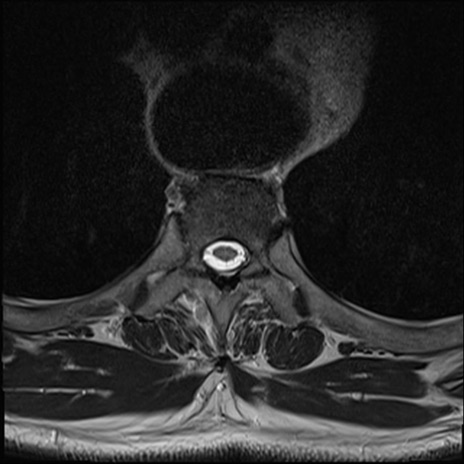

【整形】TIPS症例7 頚椎MRI T2WI(横断像)

頚椎MRI

矢状断像と横断像